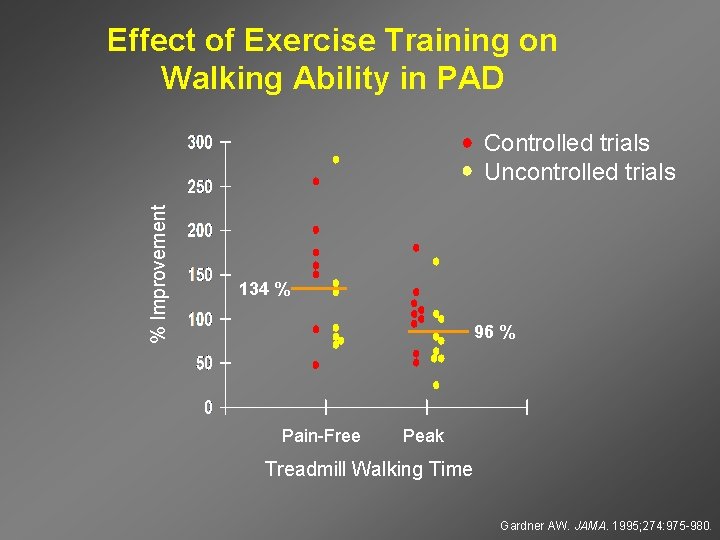

Effect of Exercise Training on Walking Ability in PAD % Improvement Controlled trials Uncontrolled trials 134 % 96 % Pain-Free Peak Treadmill Walking Time Gardner AW. JAMA. 1995; 274: 975 -980.